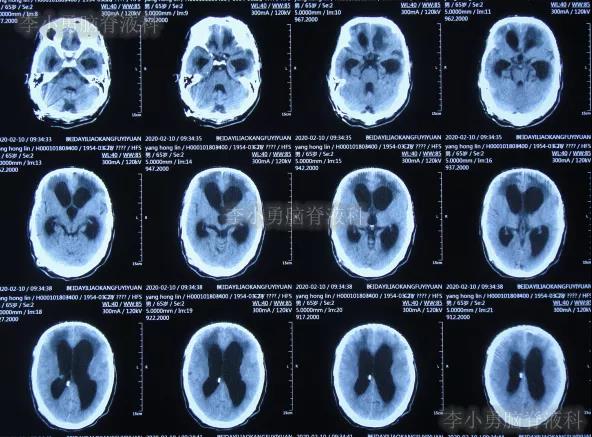

图-26:2020年2月10日头颅CT

在第4家医院治疗26天,仍间断性发热、大小便失禁加重,住院期间曾2次查头颅CT(2020年2月27日(图-28)、2020年3月12日(图-29))示脑室仍扩张。